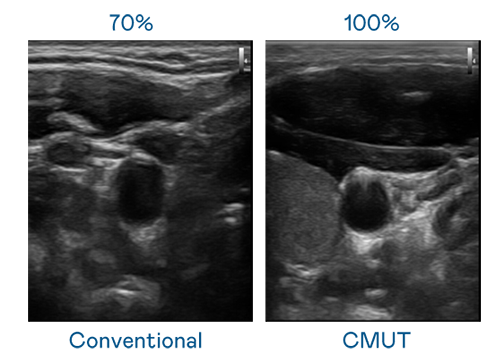

CMUT 技術是一種用電容式微機電元件來產生超音波訊號的技術。與傳統 PZT 壓電式技術相比,CMUT 頻寬增加 30%,更寬頻的超音波訊號讓影像解析度大幅提升,是實現高影像品質醫療超音波掃描、促進精準醫療發展的關鍵技術。

超音波影像的解析度高低,首先取決於探頭能發出的訊號頻寬。1277星际电子 CMUT 可提供高清晰的超音波訊號,提供高頻寬、高靈敏度、影像紋理細節更高的超音波影像,協助醫護人員縮短影像判讀時間及利用精準的醫療影像進行診斷。